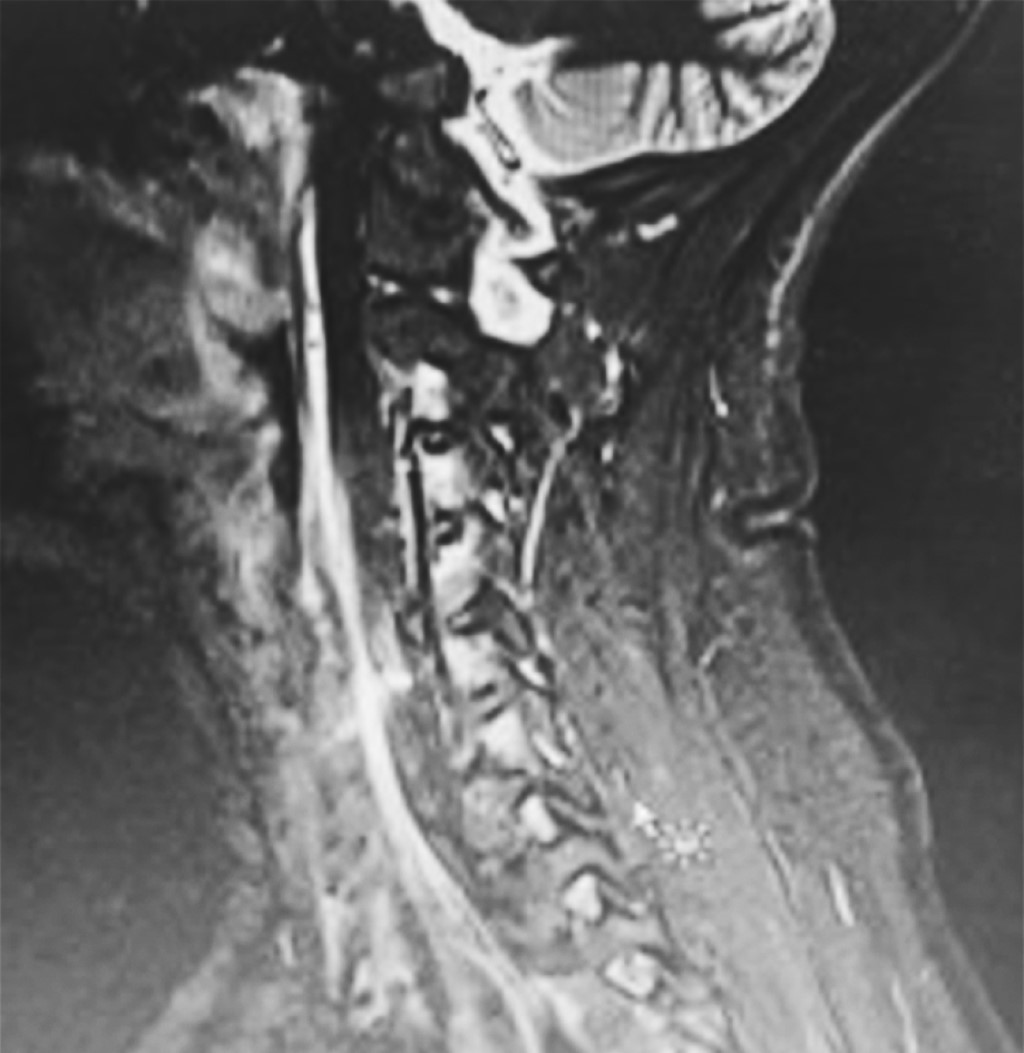

A tres pacientes se les realizó resonancia magnética de columna cervical simple (Figuras 3, 4 y 5), los días de realización variaron debido a que dos de ellos se encontraban en institución pública y la accesibilidad a la resonancia magnética no pudo ser inmediata. En los tres se presentó una hiperintensidad con forma de flecha, la cual se localizaba en el espacio prevertebral y que llegaba hasta C1-C2 (Figuras 3, 4 y 5). La hiperintensidad era isointensa respecto al líquido cefalorraquídeo que se observaba en el conducto raquídeo. En uno de los casos se pudo documentar un trayecto fistuloso, pero no fue constante en ninguno.

En los tres casos se obtuvo una segunda resonancia de seguimiento, la cual aproximadamente fue una semana después de la primera, y documentó la disminución notable del tamaño de la hiperintensidad prevertebral (Figuras 3, 4 y 5).

Como se puede observar en las imágenes previas, en la secuencia T2 en un corte sagital puede observarse una hiperintensidad en el espacio intervertebral que nos indica que en ese sitio se encuentra impregnado de líquido cefalorraquídeo, ya que la hiperintensidad es igual a la observada en el conducto raquídeo.

Como se puede observar en las imágenes previas, en la secuencia T2 en un corte sagital puede observarse una hiperintensidad en el espacio prevertebral que nos indica que en ese sitio se encuentra impregnado de líquido cefalorraquídeo, ya que la hiperintensidad es igual a la observada en el conducto raquídeo.